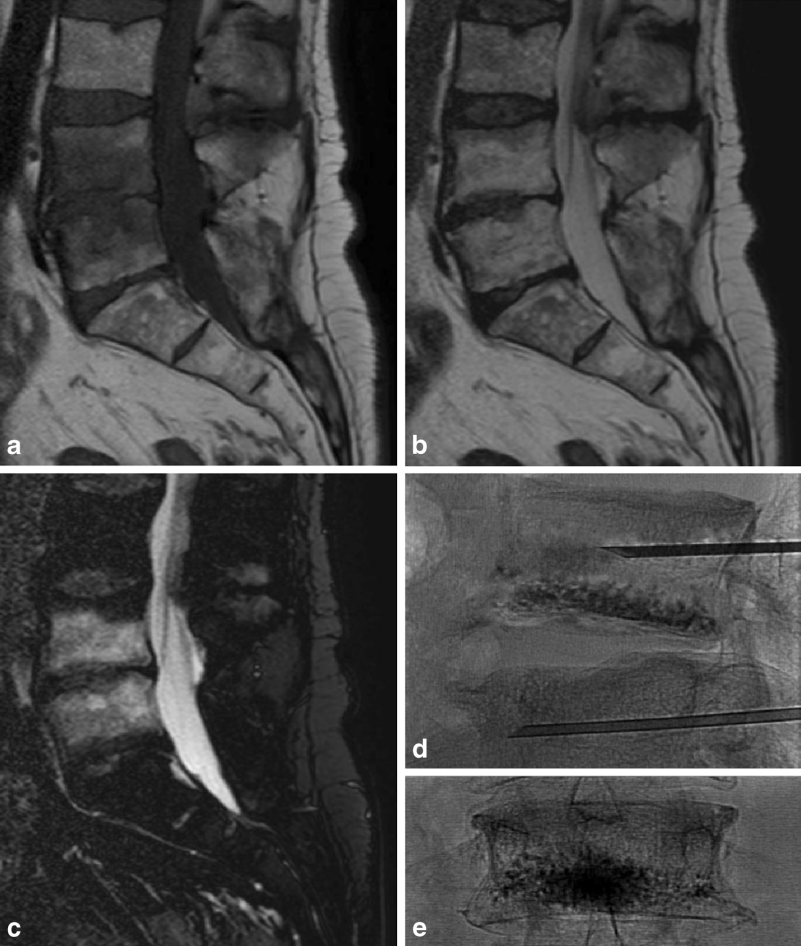

①吸收骨水泥的椎体增强术

a、b 和 c 提示 L4/5 椎体 Ⅰ 型 Modic 改变,d 提示 L4、L5 进行骨水泥注射的术中影像,e 提示术后复查 L4 椎体骨水泥填充情况。